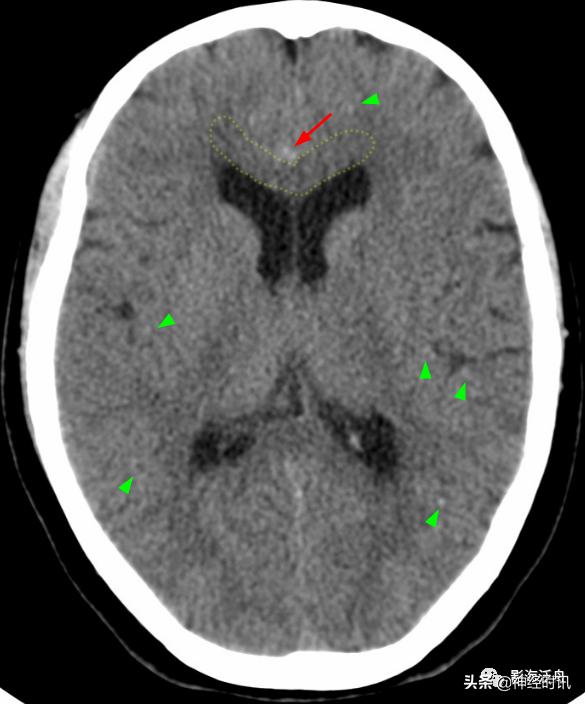

大脑镰前下部极少量蛛血(红箭),淡黄色虚线框勾勒出胼胝体膝部,血肿的边缘仍然是 模模糊糊的,注意这幅图中双侧大脑半球见多发斑点状高密度影(绿箭头),随访证实系伪影所致,而非弥漫性轴索损伤。夜班急诊时CT诊断的难点在于其密度分辨率有限(相较于MR),5mm层厚带来的容积效应干扰,有时候再加上噪声形成的伪影,就非常考验平时的基本功以及经验积累了。